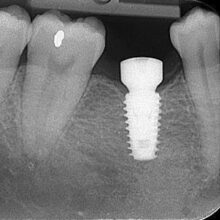

The abutment is positioned to connect the implant and the crown. The abutment is a connection that spans through the gum line, so the implant remains buried.